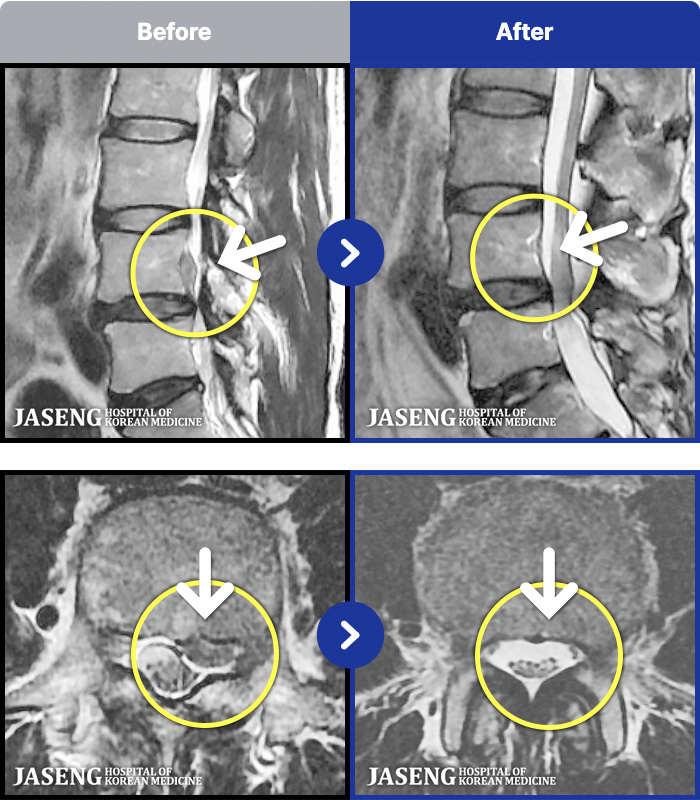

1,286 MRI ũ ʸ Ȯϼ.

[ϻ] 24.07.25~25.08.01